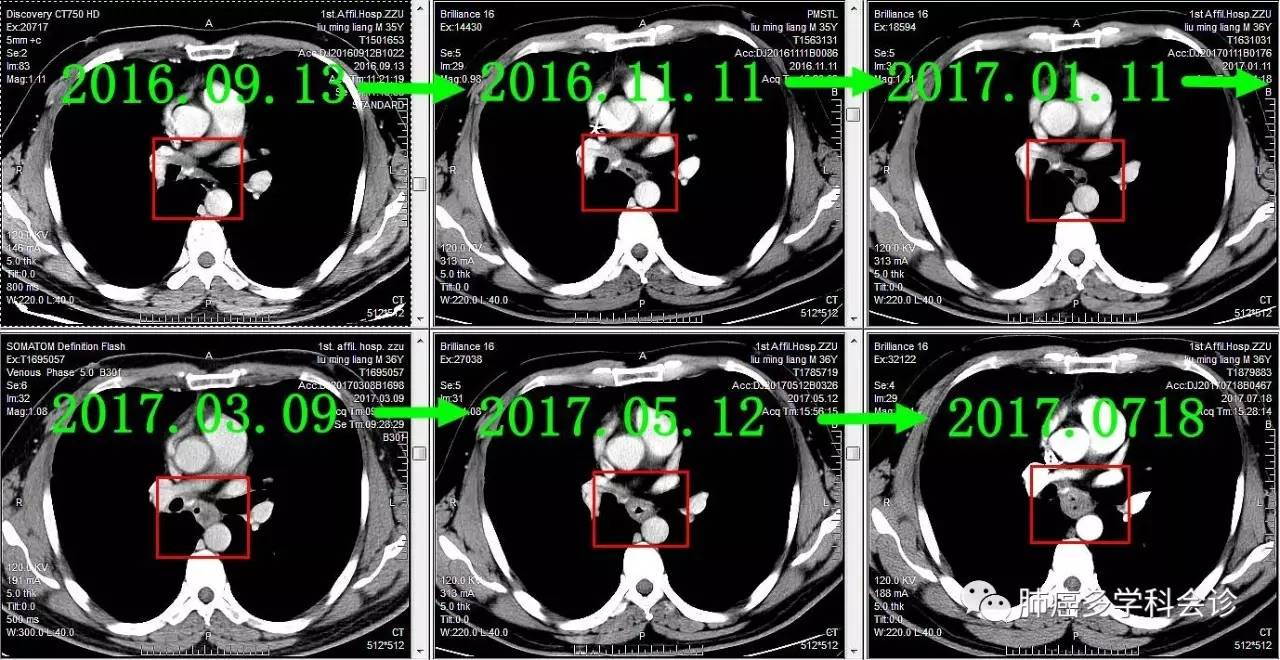

下面着重展示食管转移灶的发展过程。从2016-09-13(完成2个周期化疗)开始,上下两图分别为各时间点CT的上下两层:

食管不是肺癌的常见转移部位,容易被忽视。回顾该患者以往的胸部 CT 可见:在纵隔淋巴和原发灶逐渐退缩过程中,食管转移却逆势发展起来,反映了肿瘤对治疗反应的异质性。